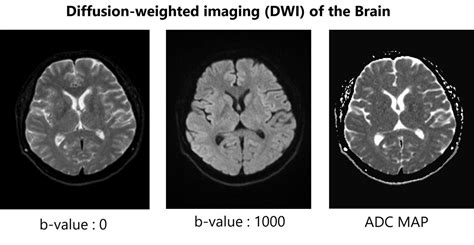

So, how do we actually get these amazing DWI images? It all comes down to understanding the DWI sequences and parameters . The most common DWI sequence is the spin-echo echo-planar imaging (SE-EPI) sequence. This is a fast imaging technique that allows us to acquire images quickly, which is crucial because patients can’t always hold their breath or stay perfectly still for long periods. The ‘echo-planar’ part means it acquires all the data for an image after just one radiofrequency excitation, making it super speedy. Now, the key to DWI is the application of diffusion gradients . These are magnetic field gradients that are intentionally applied in specific directions. We typically apply these gradients in pairs: one gradient that encourages water molecules to move (the ‘diffusion-sensitizing gradient’) and another identical gradient right after it that dephrases the signal if the molecules have moved. If the water molecules have moved significantly during the time between these gradients, their phase coherence is disrupted, and the signal intensity on the DWI image is reduced. If their movement is restricted, they remain more in phase, and the signal is preserved. The strength and duration of these gradients are controlled by a parameter called the b-value . The b-value essentially tells us how strongly the diffusion process is being probed. Low b-values (e.g., b=0 s/mm²) provide images that look more like conventional T2-weighted images and show the overall tissue signal. Higher b-values (e.g., b=1000 s/mm² or more) make the sequence highly sensitive to diffusion. DWI is typically performed with at least two different b-values (e.g., b=0 and b=1000). By acquiring images at these different b-values, we can calculate the ADC map . The ADC value quantifies the rate of diffusion. A low ADC value indicates restricted diffusion (bright on DWI), while a high ADC value indicates free diffusion (darker on DWI, assuming it’s not a T2 shine-through effect). We also need to consider diffusion directions . Water diffusion is anisotropic (direction-dependent) in some tissues, especially white matter in the brain where nerve fibers provide preferred pathways. Therefore, DWI is often performed with diffusion gradients applied in multiple directions (e.g., 6, 12, or even 32 directions) to capture this anisotropy. This is known as multi-directional DWI . Understanding these parameters – the sequence type, the b-value, and the diffusion directions – is essential for obtaining high-quality DWI scans and accurately interpreting the results. It’s a complex interplay that ultimately provides incredibly detailed information about tissue microstructure.

Interpreting Diffusion-Weighted Imaging (DWI) scans can seem a bit daunting at first, but once you understand the basic principles, it becomes much clearer. The most critical thing to remember is that restricted diffusion appears bright on DWI images . Why bright? Because the sequence is designed to attenuate the signal when water diffuses freely, and preserve the signal when diffusion is restricted. So, areas where water molecules can’t move easily – due to swollen cells, tightly packed structures, or other microstructural changes – will stand out as hyperintense, or bright, spots. The most classic example is an acute ischemic stroke . In the early minutes to hours after a stroke, brain cells become damaged, their cell membranes lose integrity, and water rushes in, causing them to swell. This swelling severely restricts the movement of water molecules. Consequently, the affected area lights up brightly on the DWI scan. This is often the very first sign of a stroke visible on MRI. However, it’s crucial to distinguish true restricted diffusion from other phenomena that can also cause bright signals. One important consideration is T2 shine-through . Some tissues naturally have a long T2 relaxation time, meaning they appear bright on conventional T2-weighted images. If these tissues also have some degree of diffusion, their signal might still appear bright on DWI, even if diffusion isn’t truly restricted. This is where the ADC map comes in as your best friend. Remember, the ADC quantifies the actual rate of water diffusion, independent of T2 effects. In areas of true restricted diffusion (like a stroke), the ADC values will be low . In contrast, areas that are bright on DWI due to T2 shine-through will have normal or even high ADC values. So, the combination of a bright DWI signal and a corresponding low ADC value is the hallmark of restricted diffusion and strongly suggests a pathological process like stroke or cytotoxic edema. Another important interpretation point is anisotropy . In tissues like the white matter of the brain, water diffusion isn’t the same in all directions. It tends to follow the direction of the nerve fibers. Multi-directional DWI and ADC tensor imaging can reveal these directional differences, which are crucial for understanding the integrity of white matter tracts. For instance, conditions that damage these tracts, like multiple sclerosis or TBI, can alter the pattern of diffusion. In tumors, DWI can help assess cellularity. Highly cellular tumors often exhibit restricted diffusion (bright on DWI, low ADC), which can help differentiate them from less cellular tumors or other lesions. So, when you’re looking at a DWI scan, always look at the DWI image and the ADC map together. The DWI highlights potential areas of concern, and the ADC map helps confirm whether the signal change is due to true diffusion restriction or something else. It’s this combined interpretation that makes DWI such a powerful diagnostic tool.